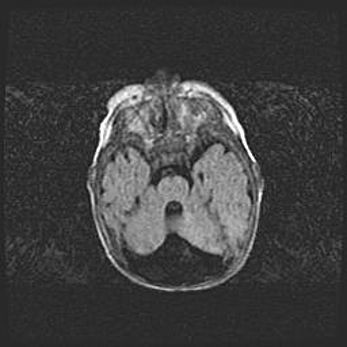

Множественные кисты обоих полушарий головного мозга, наибольшая из них в правой затылочной области. Ассиметричная атрофическая гидроцефалия.

Возраст: 7 месяцев

Вес: 5660 г

Пол: мужской

Окружность головы: 41,5 см

Срок гестации: 28-29 недель

Кисты головного мозга развиваются в результате многоочаговых некрозов вещества мозга и возникают вследствие перенесенной перинатальной инфекции, менингитов, энцефалитов, асфиксии, родовой травмы, расстройств мозгового кровообращения различного генеза. Образованию кист в веществе головного мозга плодов и новорожденных способствуют такие факторы, как высокое содержание в нем воды, недостаточная (или отсутствие) миелинизация и слабая астроглиальная реакция на повреждение.

Кисты могут сочетаться с гидроцефалией и другими поражениями головного мозга.